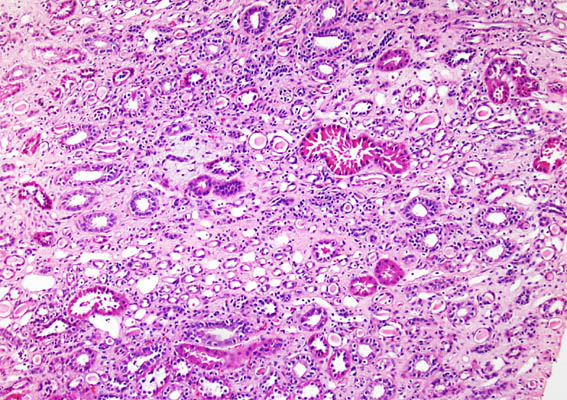

Figura 3.

H&E, X100.